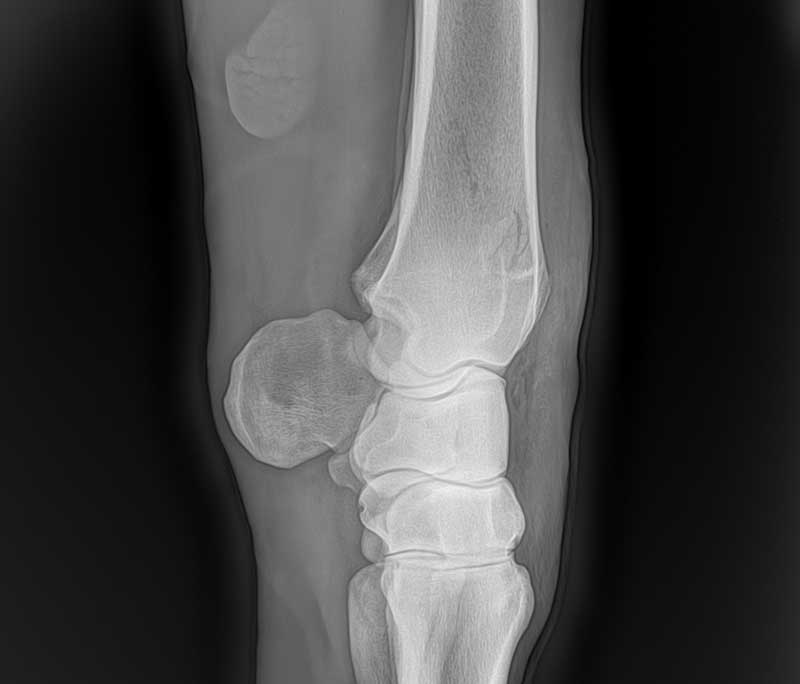

Unsere Praxis besitzt drei Systeme zur digitalen direkten Röntgenentwicklung. Ein umständliches Entwickeln der Bilder in der Praxis entfällt, innerhalb von Sekunden ist das Röntgenbild sicht- und auswertbar. Die Röntgenbilder können wir Ihnen per Email zukommen lassen.

Im Rahmen einer orthopädischen Untersuchung können wir zum Beispiel Sehnen, Sehnenscheiden oder Gelenke schallen und hierbei den Zustand der einzelne Strukturen beurteilen.